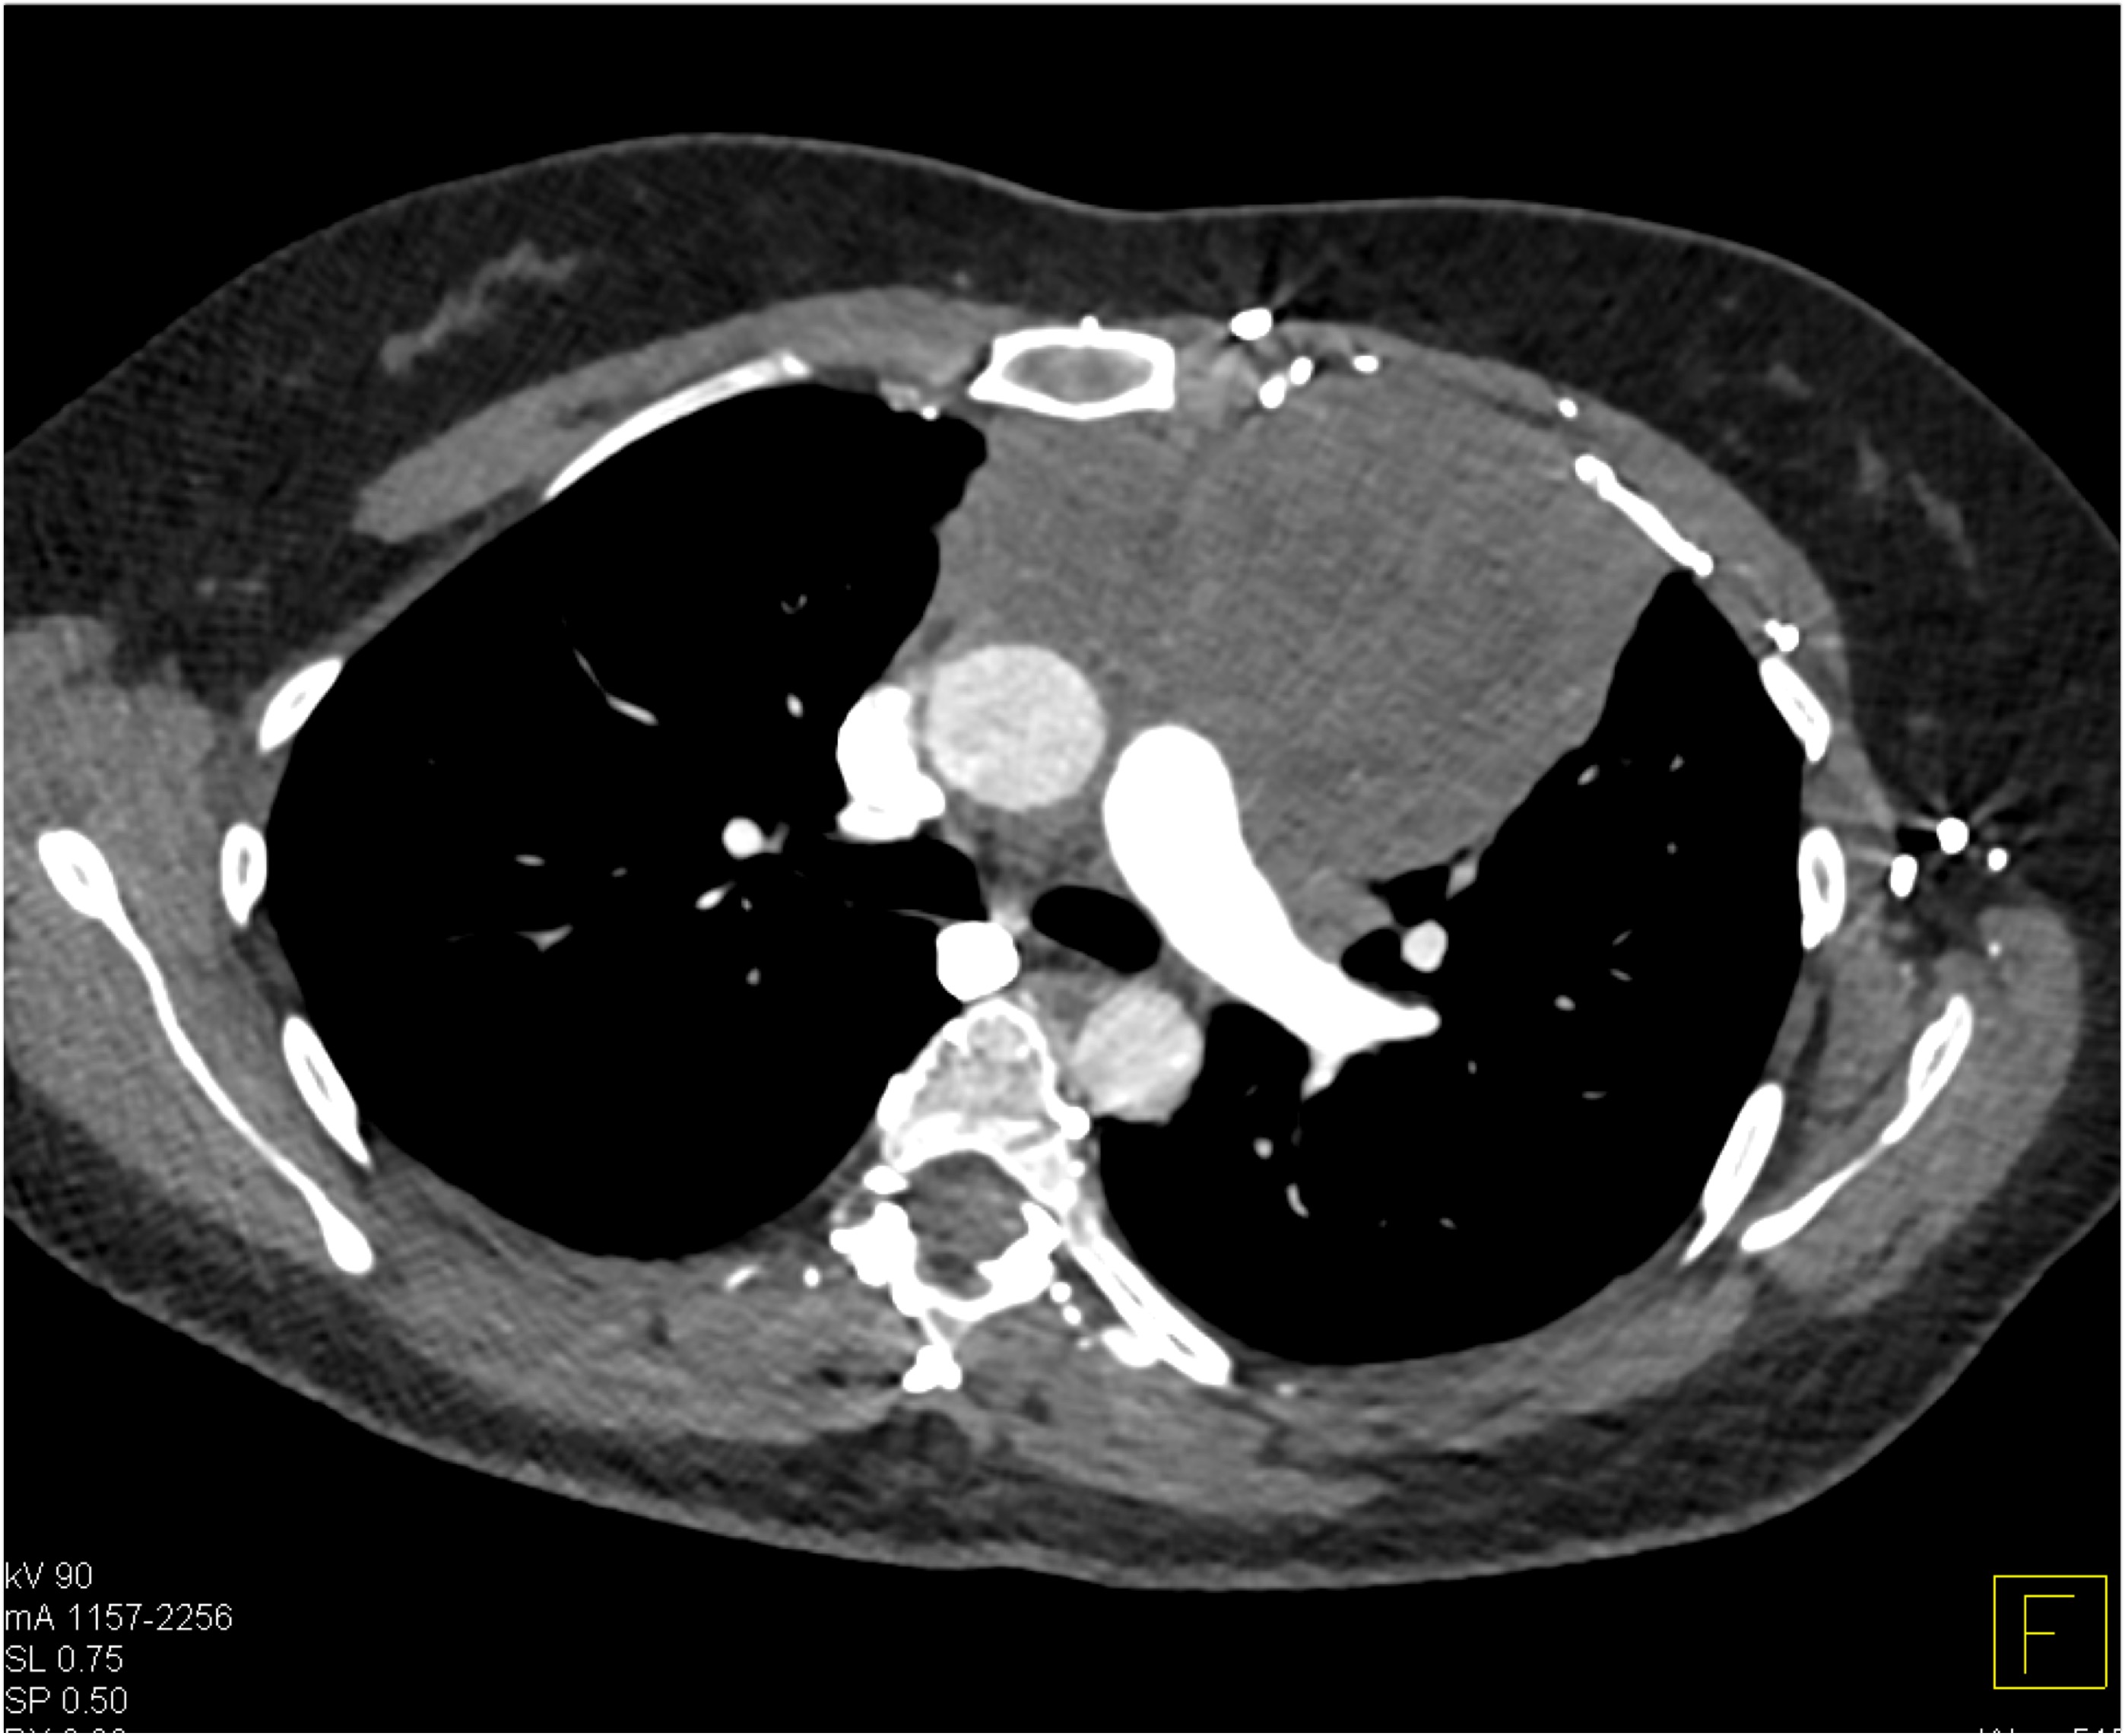

7) The most likely diagnosis in this case is?

Ehlers Danlos disease

Kawasaki disease

Takayasu’s aortitis

Ig4 vasculitis